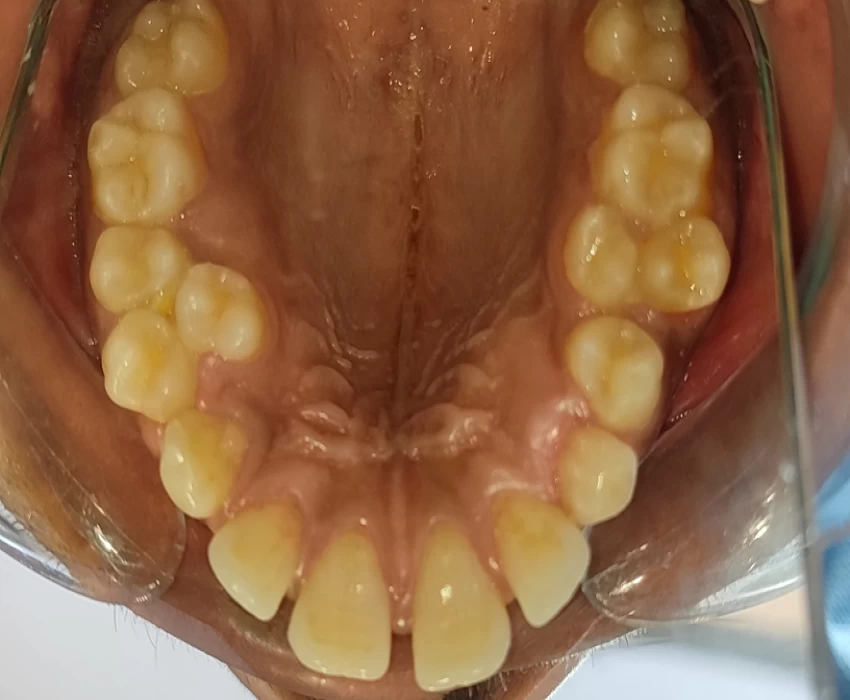

Intraoral examination revealed retained deciduous canine in the first quadrant and supernumerary premolar in the first and second quadrants of the maxilla. Mandibular arch showed missing right permanent lateral incisor.

Case was discussed and after approval of the treatment plan ,the supernumerary premolars in the first and second quadrants of the maxilla along with the retained 53 were extracted.

Patient reported after a gap of one month .It was surprising to see supernumerary canine in the first quadrant and a supernumerary premolar in the second quadrant.